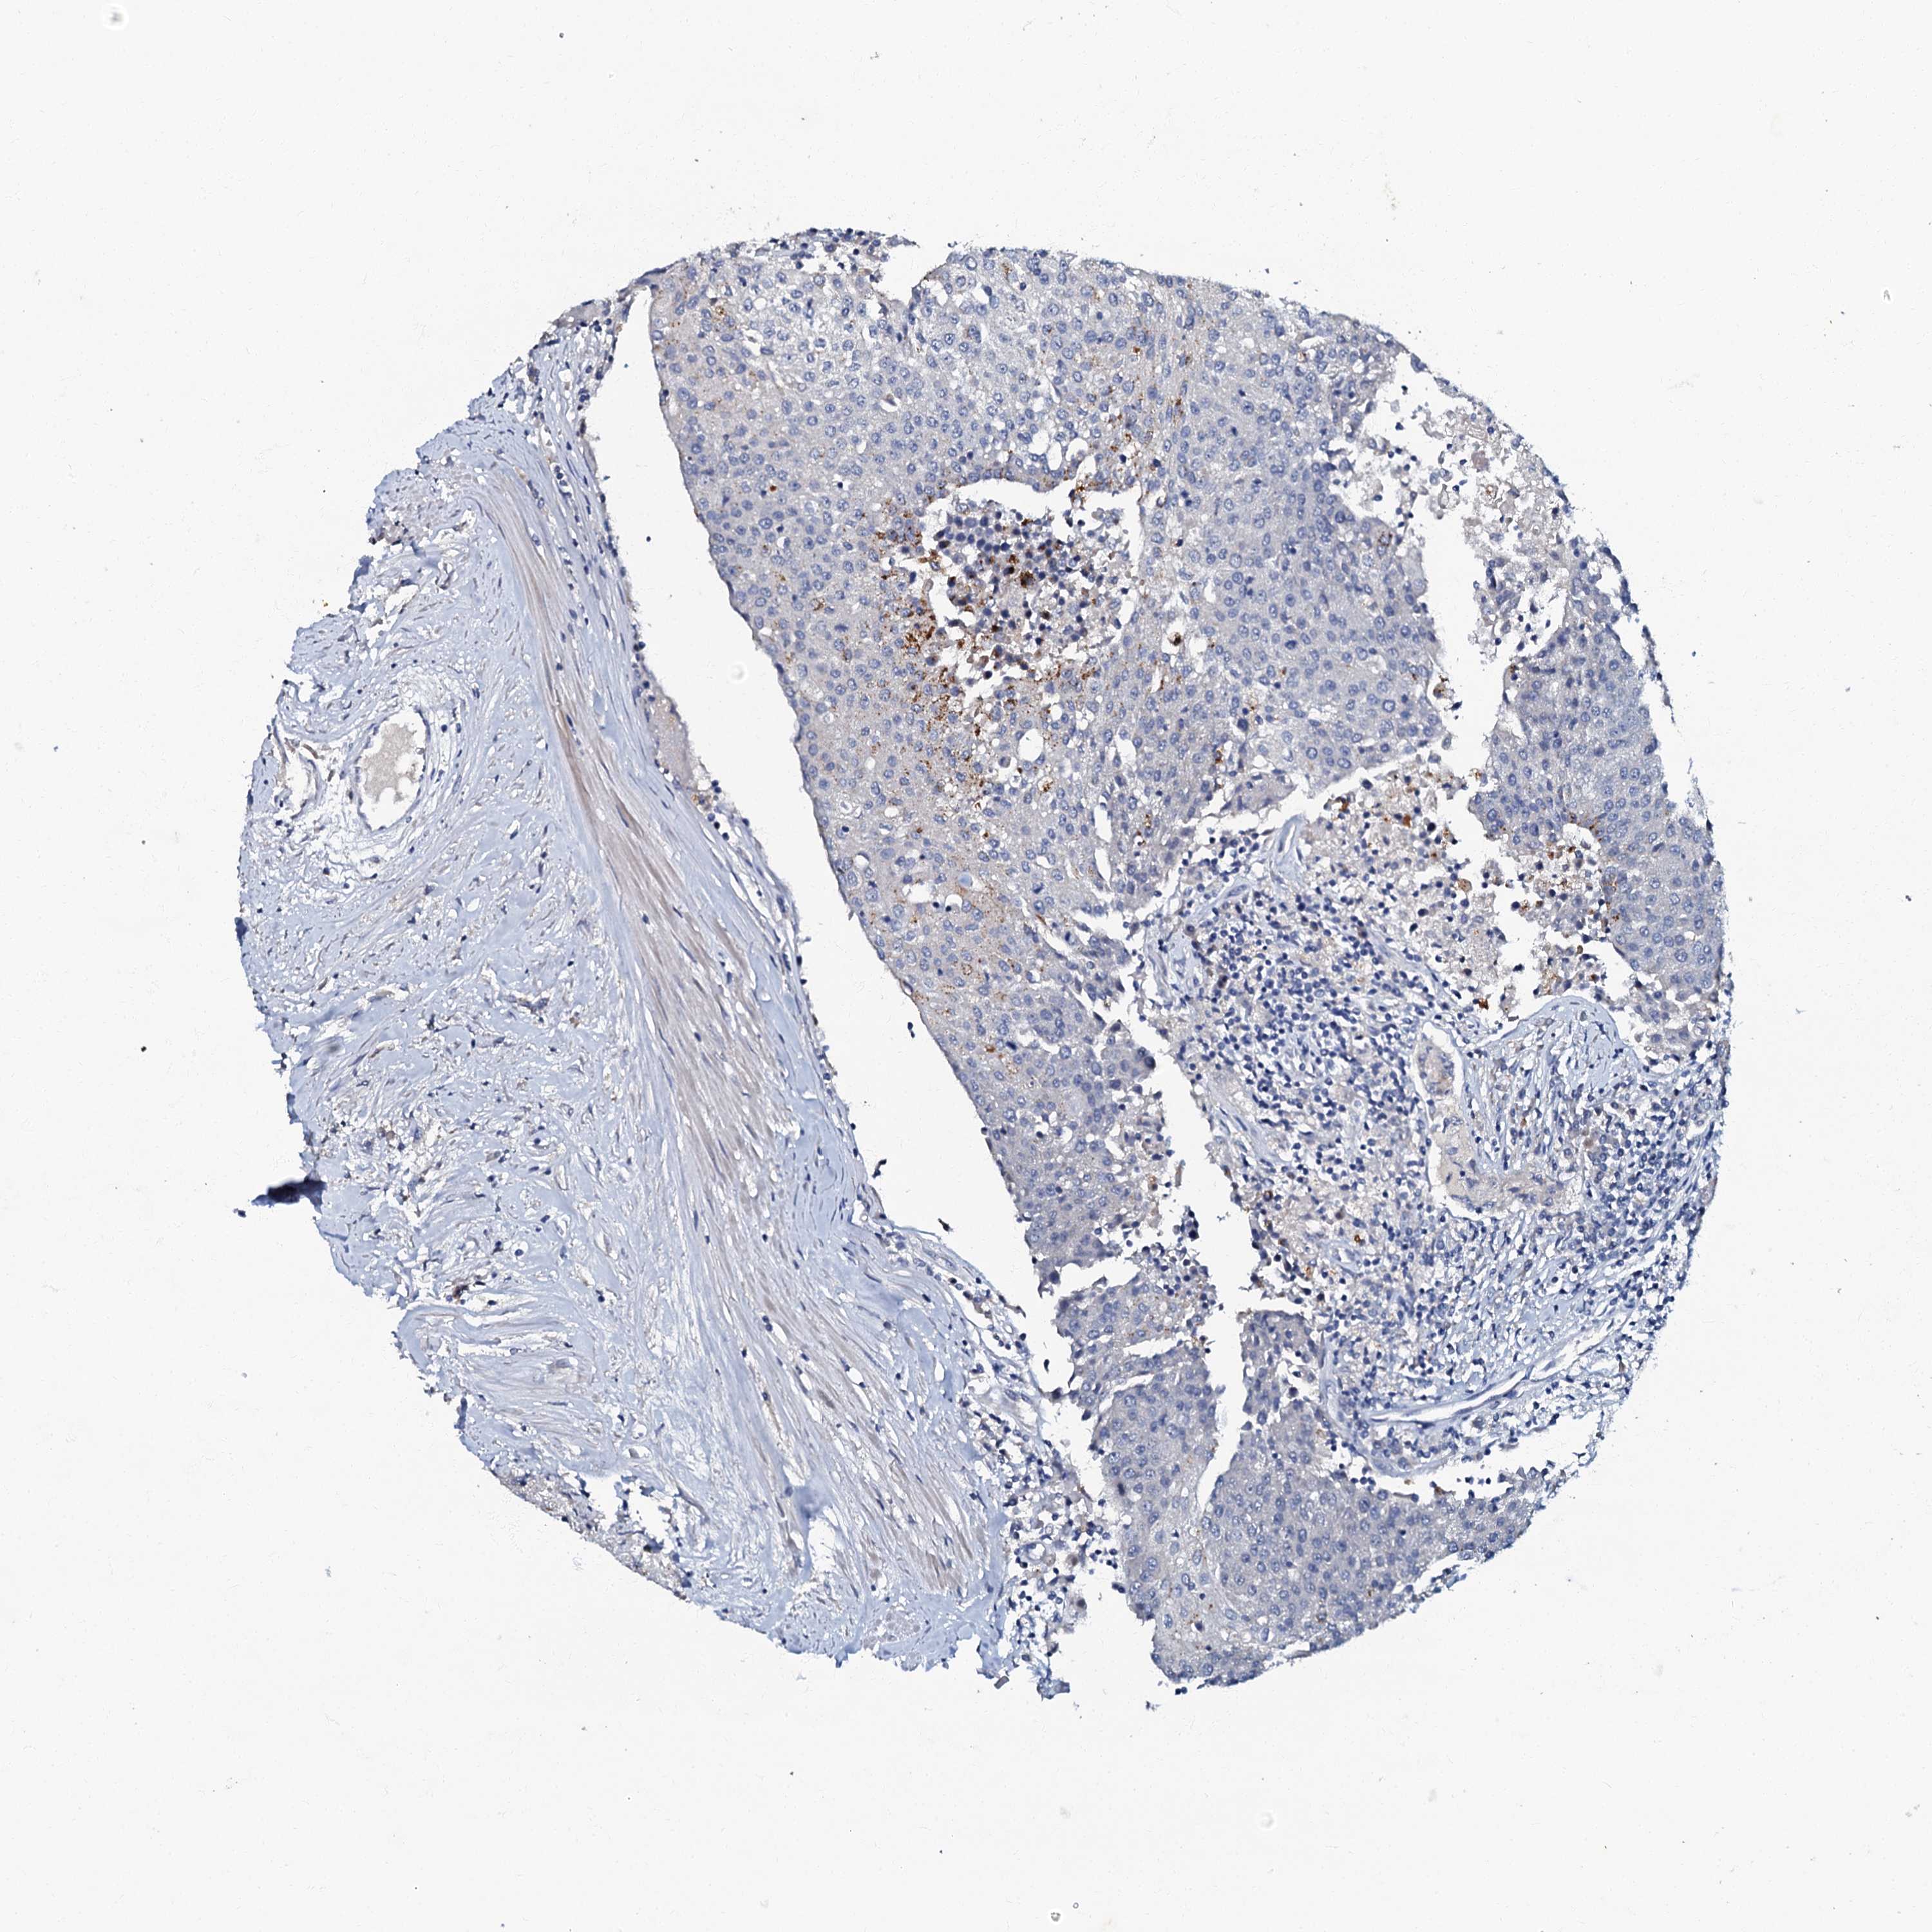

UROTHELIAL CANCER - Protein expressioni

A mouse-over function shows sample information and annotation data. Click on an image to view it in a full screen mode. Samples can be filtered based on level of antibody staining by selecting one or several of the following categories: high, medium, low and not detected. The assay and annotation is described here.

Antibody stainingi

Antibody staining in the annotated cell types in the current human tissue is reported as not detected, low, medium, or high, based on conventional immunohistochemistry profiling in selected tissues. This score is based on the combination of the staining intensity and fraction of stained cells.

Each image is clickable and will lead to virtual microscopy that enables deeper exploration of all samples and also displays staining intensity scores, fraction scores and subcellular localization as well as patient and tissue information for each sample.

Antibody HPA037947

Antibody HPA037948

Staining

High

Medium

Low

Not detected

Intensity

Strong

Moderate

Weak

Negative

Quantity

>75%

75%-25%

<25%

None

Location

Nuclear

Cytoplasmic/membranous

Cytoplasmic/membranous,nuclear

Urothelial carcinoma, High grade

Urothelial carcinoma, Low grade

Urothelial carcinoma, NOS